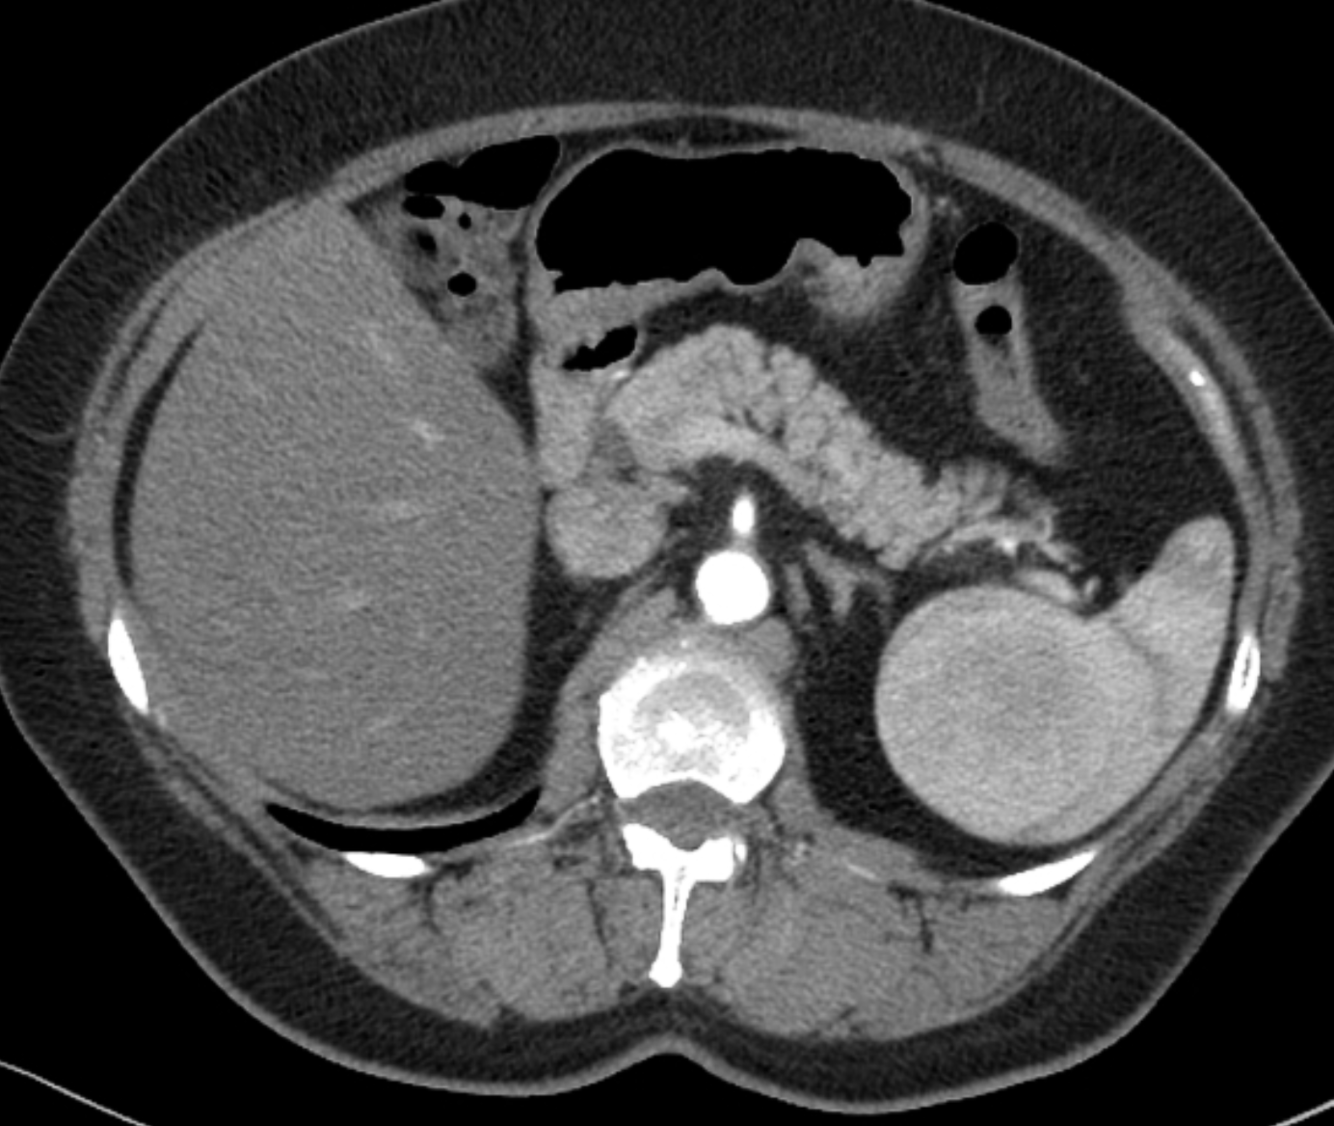

A hypodense laceration involves the posterior aspect of the spleen with intrasplenic haematoma. Right iliopsoas haematoma is noted from a fracture of the posterior right ilium and right side of sacral promontory. Mild free intraperitoneal fluid, mild bilateral basal pleural effusion and green stick fracture of left superior pubic ramus are also noted.

Diagnosis: Grade II splenic injury from blunt abdominal trauma